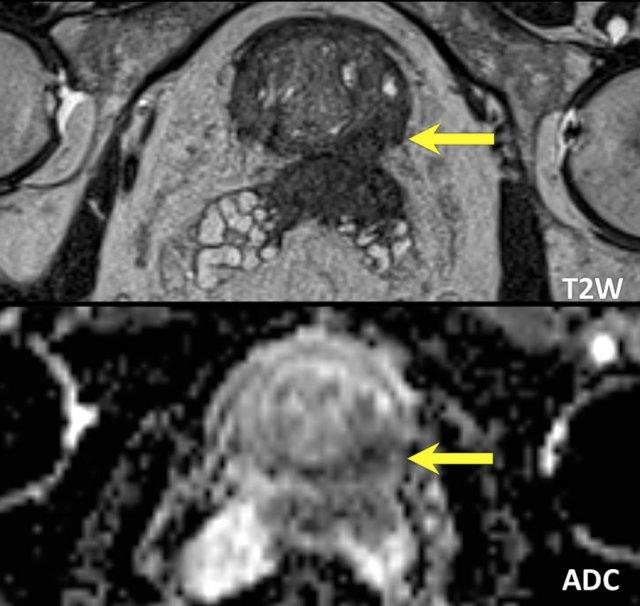

Các phát hiện bao gồm:

- Một tổn thương kích thước 17 mm (không hiển thị phép đo) nằm ở vùng ngoại vi, phía sau bên trái của phần giữa tuyến tiền liệt.

- Giảm tín hiệu rõ rệt trên ADC và tăng tín hiệu rõ rệt trên DWI.

- Tương ứng với vùng giảm tín hiệu trên chuỗi xung T2W.

- Trên chuỗi xung T2W, tổn thương tiếp xúc diện rộng với vỏ bao tuyến tiền liệt.

Tổn thương này được xếp vào phân loại PI-RADS 5 với nghi ngờ xâm lấn ra ngoài tuyến tiền liệt.

Điểm Gleason là 4+3.

Tổn thương nghi ngờ này có hạn chế khuếch tán đáng kể.

Giá trị ADC đo được là 440 mm²/s.

Giá trị ADC thấp cho thấy nguy cơ ác tính cao hơn.

Giá trị ADC thực tế có tương quan nghịch với khả năng ác tính có ý nghĩa lâm sàng.

Các giá trị trên 900 mm²/s được coi là có khả năng lành tính và dưới 750 mm²/s có khả năng ác tính.

Tuy nhiên, kết quả định lượng có thể khác nhau đáng kể giữa các máy chụp và các giao thức chụp.